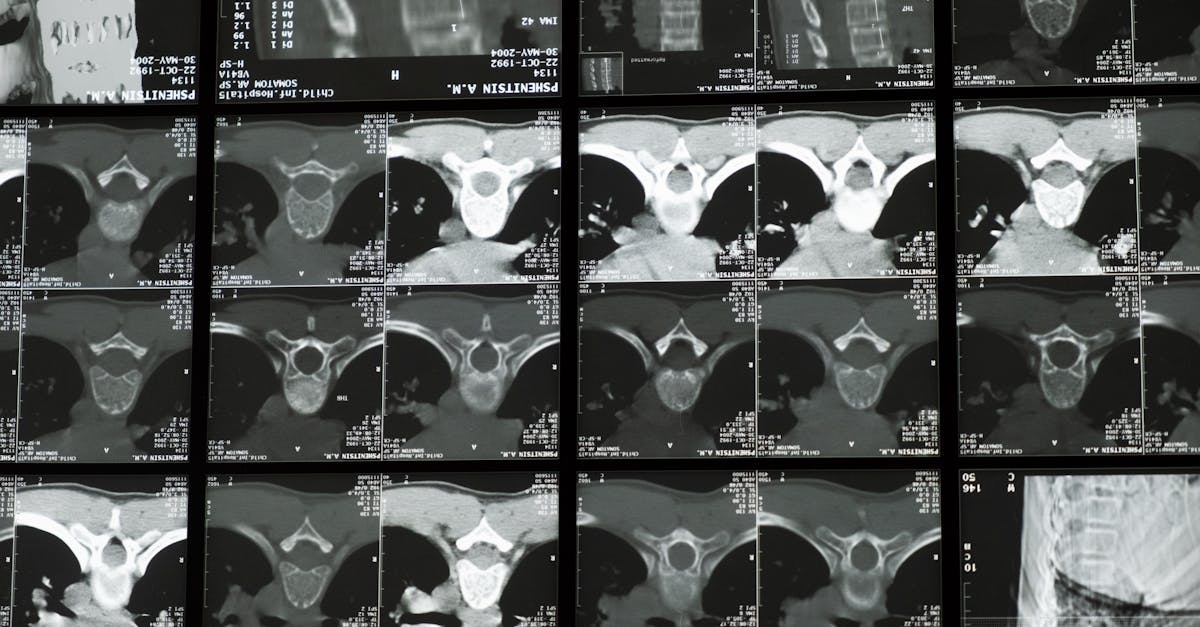

La escoliosis, una afección caracterizada por una curvatura lateral anormal de la columna, afecta a las personas de diversas maneras, desde molestias leves hasta complicaciones graves. Quienes viven con escoliosis a menudo buscan estrategias efectivas para controlar su afección y mantener una postura estable y equilibrada. En Montreal, expertos como el Dr. Sylvain Desforges están a la vanguardia del desarrollo de enfoques innovadores para tratar la escoliosis y mejorar el bienestar general.

El Dr. Desforges es reconocido como una figura destacada en el campo de la osteopatía, la naturopatía y la medicina manual. Como presidente fundador de las clínicas TAGMED, ha dedicado su carrera a la innovación sanitaria. Centrándose en el manejo del dolor crónico, el Dr. Desforges ha integrado en su práctica tecnologías de tratamiento avanzadas como descompresión espinal, terapia con láser y terapia con ondas de choque. A través de su enfoque multifacético, su objetivo es brindar atención basada en evidencia y adaptada a las distintas necesidades de cada paciente.

Un aspecto clave de la metodología del Dr. Desforges es el énfasis en autocuidado y ejercicio para personas con escoliosis. Aboga por un régimen de ejercicio integral que mejore fuerza central y estabiliza la alineación de la columna. Por ejemplo, actividades como el entrenamiento del equilibrio con un entrenador de equilibrio BOSU o ejercicios de fisioterapia específicos son fundamentales para controlar la escoliosis. Estas estrategias sirven no sólo para aliviar los síntomas sino también para mejorar la estabilidad general y contribuir a mejoras de salud a largo plazo.